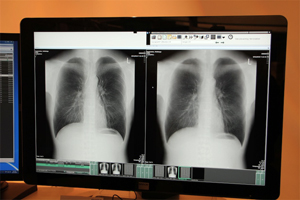

FPDの画像解析アプリケーションでは,富士フイルムのデジタル技術を生かしたトモシンセシス,エネルギーサブトラクションが紹介された。ともにRSNA2012開催直前にFDAの認可を受けたとのことだ。エネルギーサブトラクションでは,呼吸や心臓の動きによる画像のズレを認識して自動補正することで,正確なサブトラクションが行えることをアピールした。

エネルギーサブトラクション |